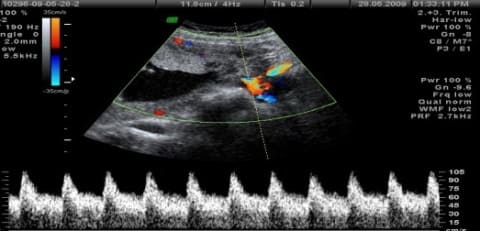

- УЗИ+допплерометрия – визуальный метод исследования, допплерометрическое сканирование показывает кровоток в сосудах матки, пуповине и сосудах плода.